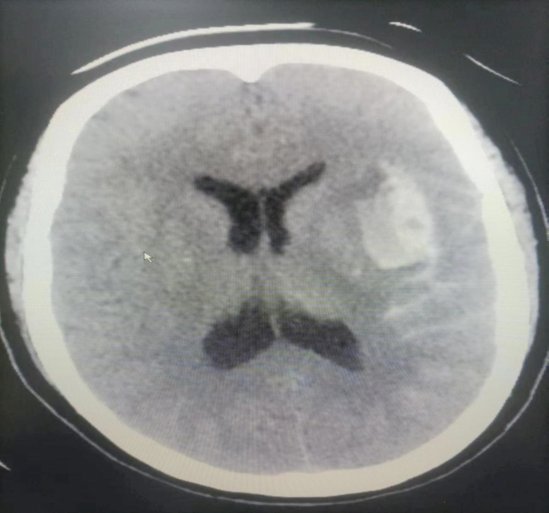

▲CT:左颞叶血肿

▲CTA:左侧大脑中动脉瘤,形态不规则

诊断明确,左颞叶血肿、蛛网膜下腔出血为左侧大脑中动脉分叉处动脉瘤破裂出血所致,病情危重,动脉瘤随时有再次破裂出血危及生命可能,我科手术团队立即展开病情讨论,结合患者病灶位置、动脉瘤形态、周围血管关系、经济等情况,综合评估后认为开颅动脉瘤夹闭术优于血管内介入治疗,经手术风险告知、签字同意后急诊实施开颅脑动脉瘤夹闭术。